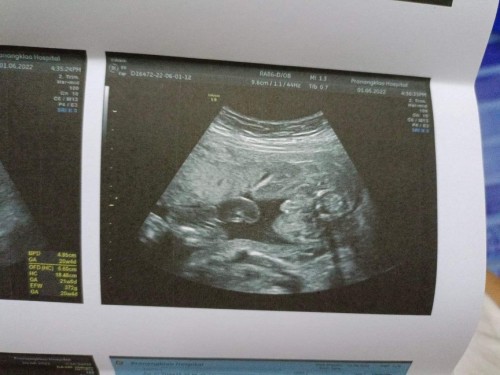

แม่ๆบ้านไหน ดูเพศน้องออกบ้างค่ะ

20สัปดาห์6วัน ท้อง3 ทีมตุลาจ้า 🤗

ผู้หญิงค่ะ

แต่หมอบอก ผช.90%คะ น้องโชว์จู๋เลยค่ะแม่